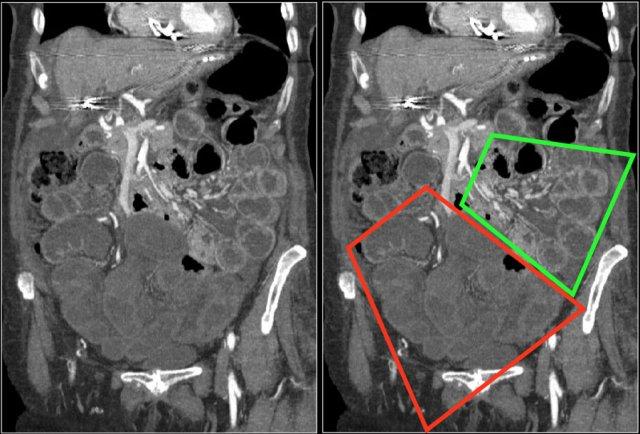

Đôi khi, tái tạo ảnh mặt phẳng coronal dạng lát cắt dày (thick slab coronal reconstructions) có thể hữu ích trong việc đánh giá mức độ ngấm thuốc.

Điều này được minh họa rõ ràng ở bệnh nhân này, trong đó hỗng tràng ngấm thuốc tốt (vùng xanh lá), trong khi hồi tràng giảm ngấm thuốc (vùng đỏ) do thiếu máu cục bộ.

Đây là một trường hợp tắc ruột quai kín khác.

Lưu ý sự khác biệt về mức độ ngấm thuốc giữa các quai ruột bình thường không giãn (mũi tên xanh lá) và các quai ruột giãn bị thắt nghẹt (mũi tên đỏ).

Ở trung tâm là các mạch máu mạc treo bị xoắn vặn (mũi tên vàng).